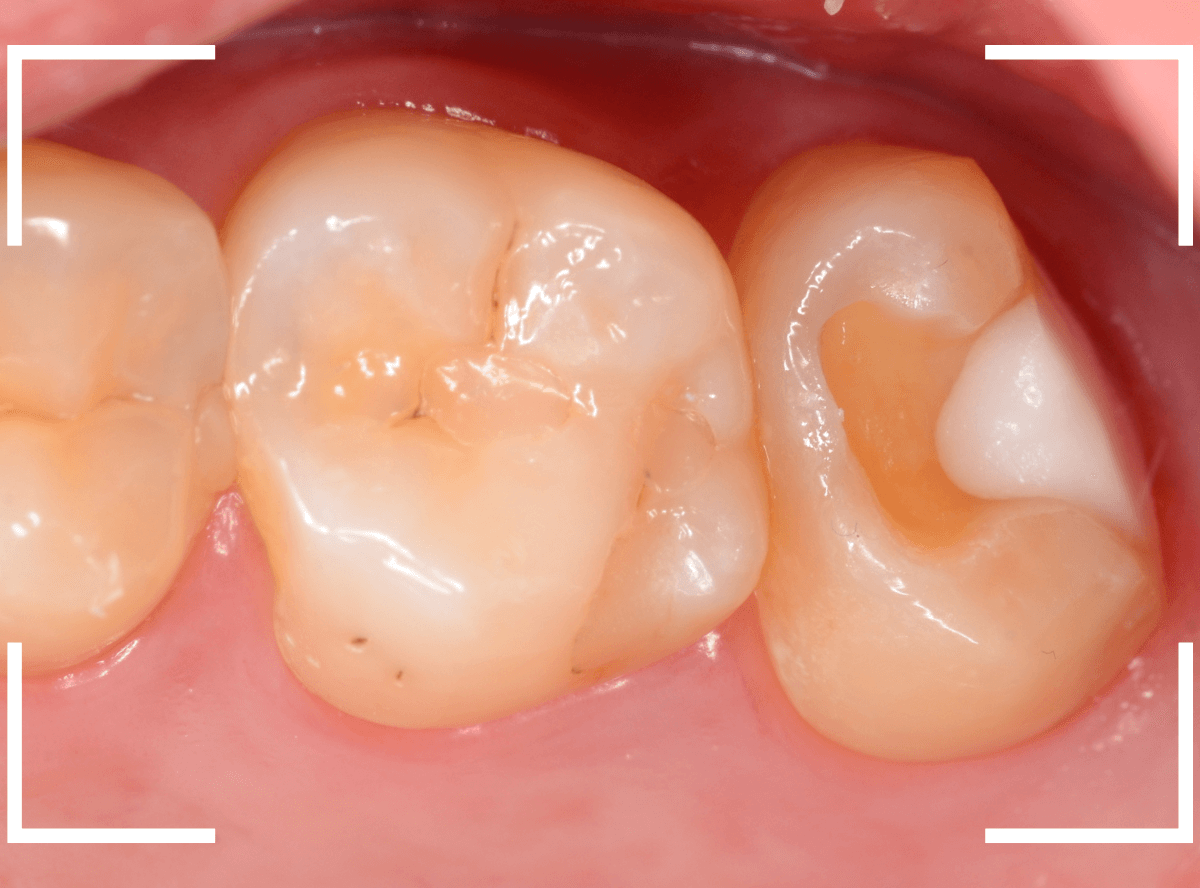

今回は、「上の奥歯が噛むと痛い」という訴えで来院された患者さんのケースです。

初見では、どこが悪いのかはっきりわかりません。

レントゲン写真で確認すると、 奥歯はどの歯も深い虫歯ですが、特に、奥から2番目の歯が深い虫歯で、痛みの原因だと思われます。

痛みが出るまで様子見た虫歯はどうなっているのでしょうか。